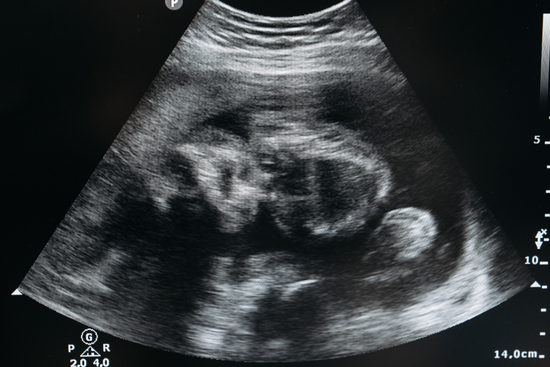

Just two months after starting my new thyroid medication and tracking ovulation with Mira, I got pregnant! My husband and I are now more than halfway to meeting our sweet baby boy. It's amazing to think that this success was possible thanks to Mira and understanding my hormone health better.